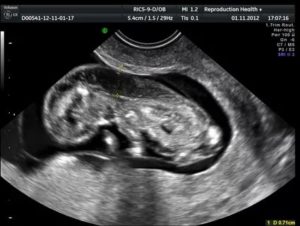

УЗИ

Ультразвуковое исследование считается достаточно точным и информативным методом установления заболевания.

С помощью современной аппаратуры специалисту удается определить структуру, локализацию, размер новообразования.

На основе результатов УЗИ происходит дифференцированная диагностика. Гигромы следует отличить от опухолей иного типа и ракового поражения.

Ультразвуковое исследование также позволяет выявить патологию на ранних стадиях развития новообразования.Назначается в случаях, когда диагностирована множественная гигрома. Благодаря послойному сканированию образования удается уточнить его структуру, консистенцию содержимого, расположение относительного нервных окончаний и сосудистым узлам.

Специального исследования направленного на выявление развития данного типа патологий плода не существует. Шейную гигрому плода диагностируют во время проведения ультразвукового исследования (УЗИ) первого триместра беременности на сроке в 12 недель.

Основным свидетельством о наличии у будущего малыша кистозной гигромы являются отклонения в размерах воротниковой зоны эмбриона. При проведении современной УЗИ диагностики измерить толщину воротниковой зоны не представляет особого труда, основываясь на результатах исследования опытный специалист может определить вероятность развития ламфангиомы у плода.

На боле поздних сроках о развитии шейной гигромы плода свидетельствует наличие ассиметричных образований с тонкими стенками, окруженных серозной оболочкой, основное место локализации таких образований — это шейный отдел позвоночника.

Также изображения полученное в результате УЗИ следует оценивать при большом увеличении. Если в момент исследования эмбрион находиться в положении, которое затрудняет провести оценку размеров воротникового пространства, необходимо дождаться проявления двигательной активности, чтобы получить точные данные.